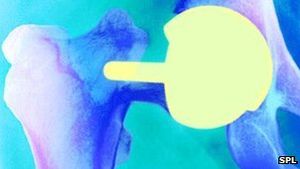

Oberflächenersatz: nur Teile werden ersetzt (Foto: SPL) |

Bristol (pte011/02.10.2012/10:25) Eine Operation, die statt eines Ersatzes des Hüftgelenks durchgeführt wird, hat eine hohe Ausfallrate und sollte in den meisten Fällen laut Wissenschaftlern der University of Bristol http://bris.ac.uk nicht mehr durchgeführt werden. Die Empfehlungen des Teams um Ashley Blom basieren auf der Analyse der Daten der National Joint Registry http://bit.ly/UDgJnf , der größten Datenbank zu Operationen in diesem Bereich. Bei einem Oberflächenersatz am Hüftgelenk wird der geschädigte Knochen abgedeckt und nicht ersetzt.

Die Wissenschaftler gehen jedoch davon aus, dass das gleiche theoretische Sicherheitsrisiko bestehen könnte. Die Forscher konzentrierten sich auf die Ausfallsraten bei einem Oberflächenersatz aus Metall. Dabei erhalten nur die Gelenkspfanne und der Knochen einen Überzug aus Metall. Bei rund sieben von 100 Patienten wird ein Oberflächenersatz und kein vollständiger Ersatz des Gelenks durchgeführt. Die Anzahl dieser Eingriffe ist jedoch in den vergangenen Jahren zurückgegangen. Bei rund 32.000 Personen wurde dieser Eingriff in England und Wales zwischen April 2003 und September 2011 durchgeführt.